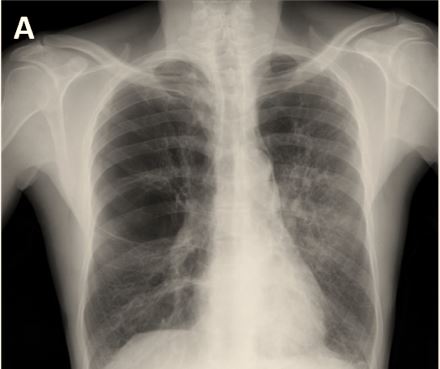

The authors of this article aimed to describe the imaging features in smoking-related lung diseases and how the pathological manifestations translate on high-resolution computerized tomography.

Article: Diffuse smoking-related lung diseases: insights from a radiologic-pathologic correlation